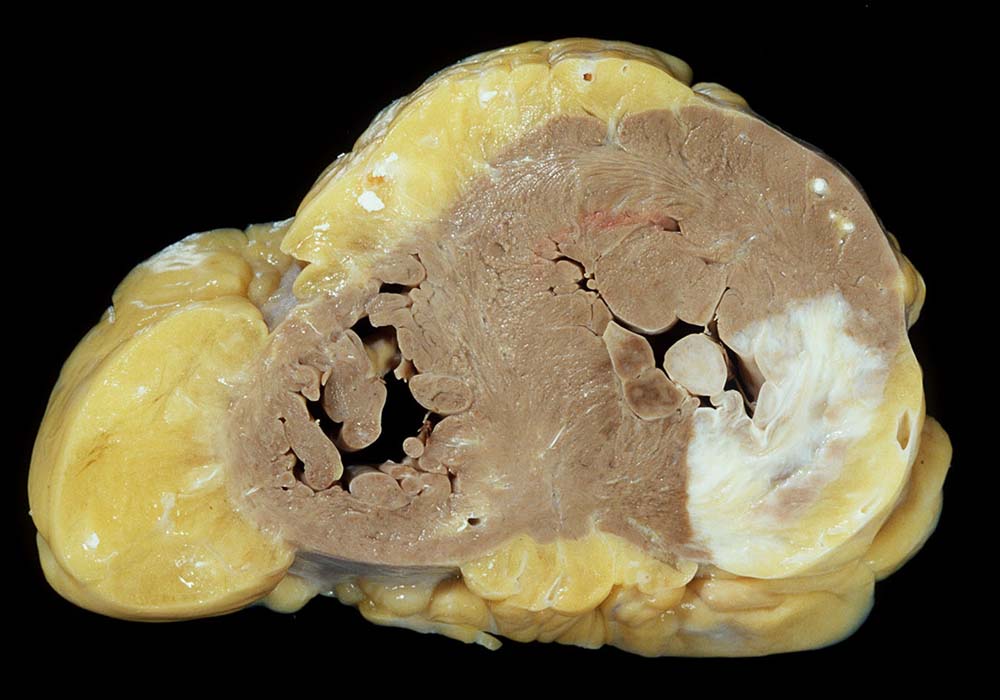

Komplikationen:

Im Bereich grösserer Narben ist das Myokard verdünnt. Bei 8% der transmuralen Infarkte entsteht im Bereich der Narbe ein Herzwandaneurysma (> 2088) mit oder ohne wandständige Thrombose (> 348). In 5-15% führen die Thromben zu systemischen Embolien. Von der Randzone der Aneurysmen gehen oft hartnäckige ventrikuläre Rhythmusstörungen aus. Grosse Narben führen zu einer Verminderung der Pumpleistung mit Herzinsuffizienz.